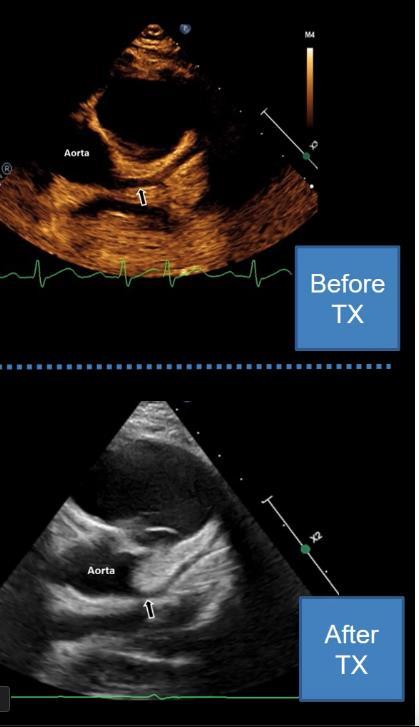

MIS-C Embolism

Imaging of Covid 19 infection in children

MIS-C: Heart failure

60 Embolus Imaging of Covid 19 infection in children

MIS-C

61